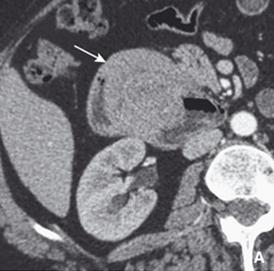

Image TDM en coupe axiale :

Invagination duodenoduodenale par un polyp duodenale

( fleche blannche ) |

|

Meme cas en coupe coronale . |